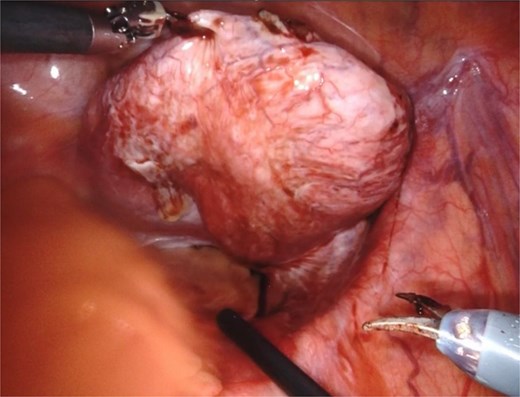

Based on the patient’s symptoms and imaging findings, robotic-assisted laparoscopic excision of the right seminal vesicle cyst was planned. The procedure was performed under general anesthesia using a da Vinci surgical system with a four-port approach. The patient was positioned in steep Trendelenburg position. A large right seminal vesicle cyst was identified posterior to the bladder (Fig. 2). Meticulous dissection was performed to separate the cyst from surrounding structures. The cyst contents were aspirated, yielding 150 cc of brownish fluid (Fig. 3). Complete excision was achieved while preserving the bladder neck, left ureter, and neurovascular bundles. Hem-o-lok clips were applied to secure the base of the cyst. Complete hemostasis was achieved, and there were no intraoperative complications.

The seminal vesicle cyst after dissection of surrounding tissue and fluid aspiration (150 cc).